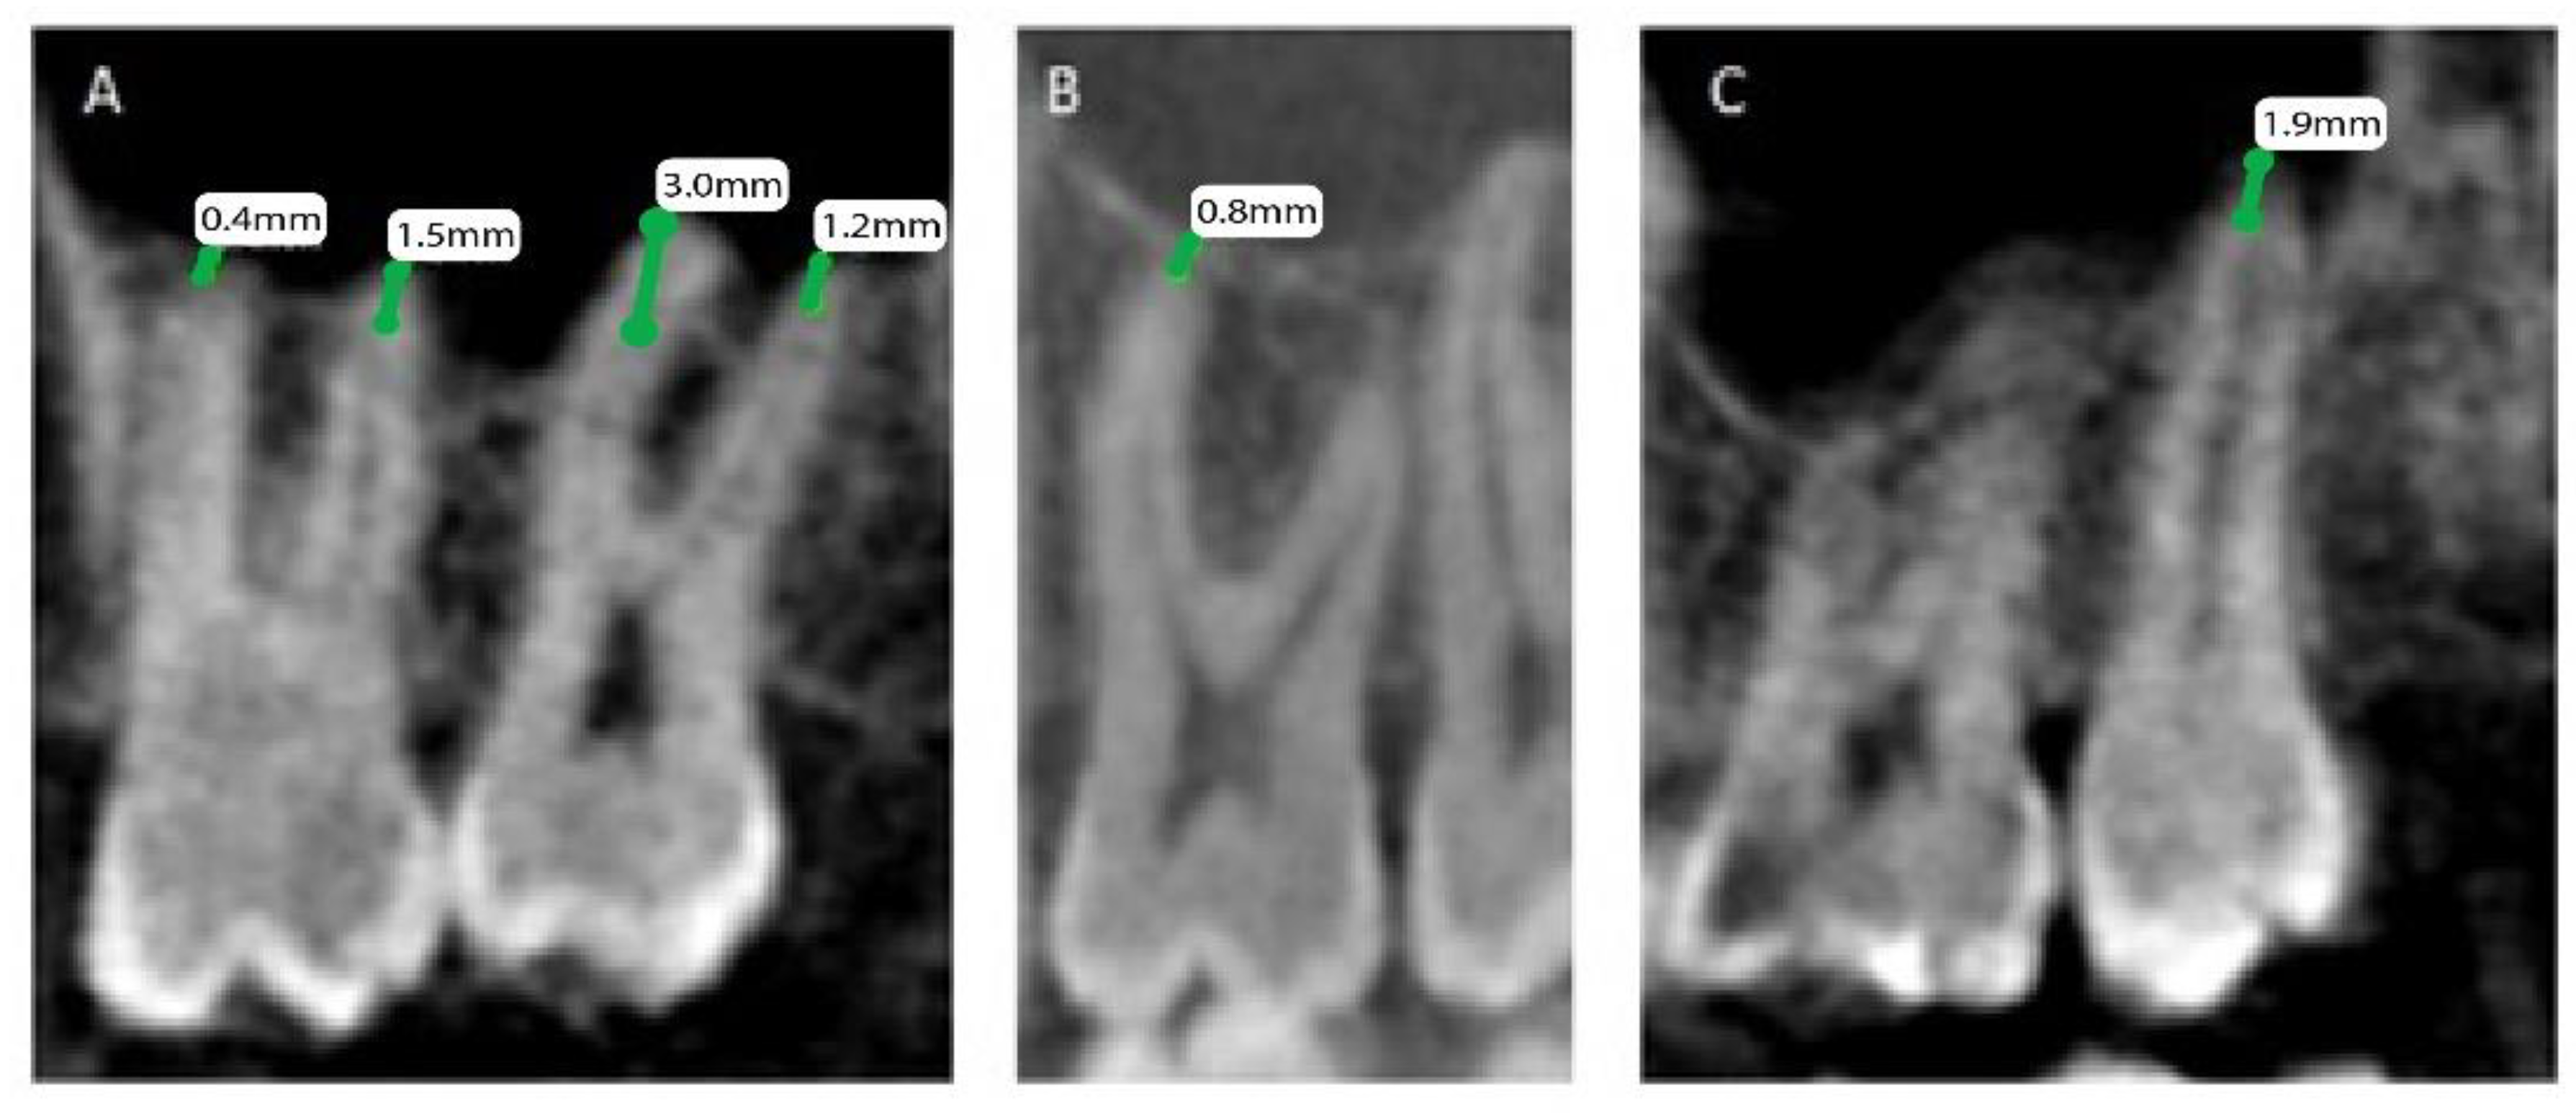

The patients’ files were assessed by the Department of Oral & Maxillofacial Surgery and Diagnostic Sciences, College of Dentistry, Prince Sattam Bin Abdulaziz University, Al-Kharj, Saudi Arabia, to record the gender and the age of the subjects included in the study from September 2020 to December 2020, and further divided as male and female patients, depending on gender and age, into 4 groups (0 to 20, 21 to 40, 41 to 60, and above 60). Mean distances between posterior maxillary roots (PMRs) from different teeth and the maxillary sinus floor (MSF) were measured using a software-calibrated tool. Each measurement was obtained by measuring a line drawn from the MSF to the nearest point of the apex of the root in two views, sagittal and coronal, and the mean distance was calculated (Figure 1, Figure 2 and Figure 3). The distance for each root and each tooth were recorded and transferred to the Excel sheet.

Figure 3.

CBCT sagittal view showing the distance between the maxillary sinus and the root of permanent maxillary. (A) Right first and second molars with mesiobuccal and distobuccal roots, (B) left first molar mesiobuccal root, and (C) left second molar palatal root.